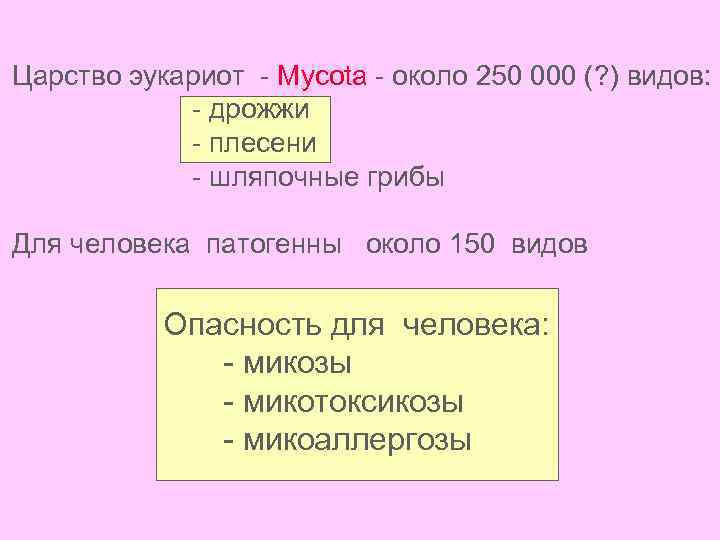

Царство эукариот - Mycota - около 250 000 (? ) видов: - дрожжи - плесени - шляпочные грибы Для человека патогенны около 150 видов Опасность для человека: - микозы - микотоксикозы - микоаллергозы